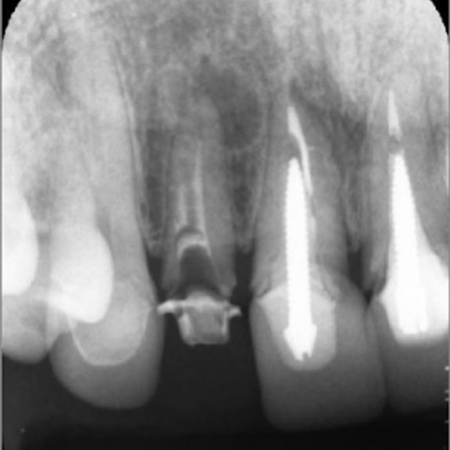

レントゲン撮影をして詳しく拝見したところ、右上前歯は神経や血管が通る根管に清掃と消毒を行う「根管治療」が施されていましたが、本来根管がある部位とは違う場所を削り、誤って穴を開けてしまう「パーフォレーション」が起きていました。

このパーフォレーションが原因で、間違った方向に違う根管を作ってしまっている状態です。

さらに歯の内部に細菌が侵入して炎症を起こし、歯根の先に膿が溜まる根尖病巣(こんせんびょうそう)も認められます。